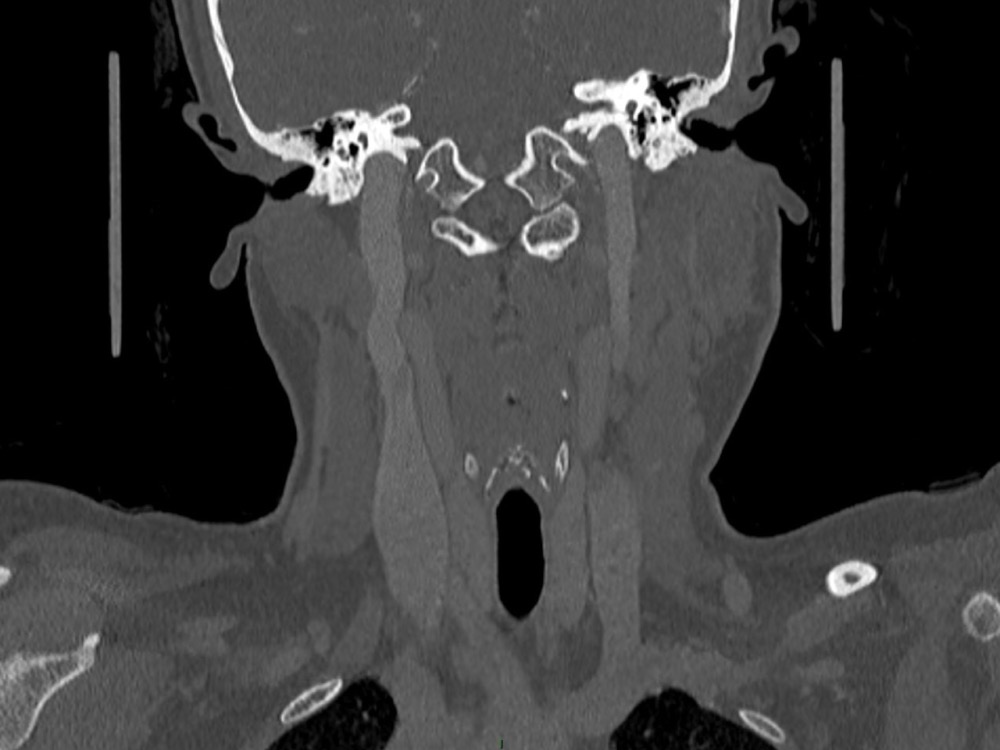

Arsovic / Perrot / Miquel 18/05/2022